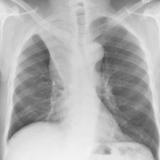

Gallery Lobar Collapse

Lobar Collapse

LUL Collapse

Album: LUL Collapse